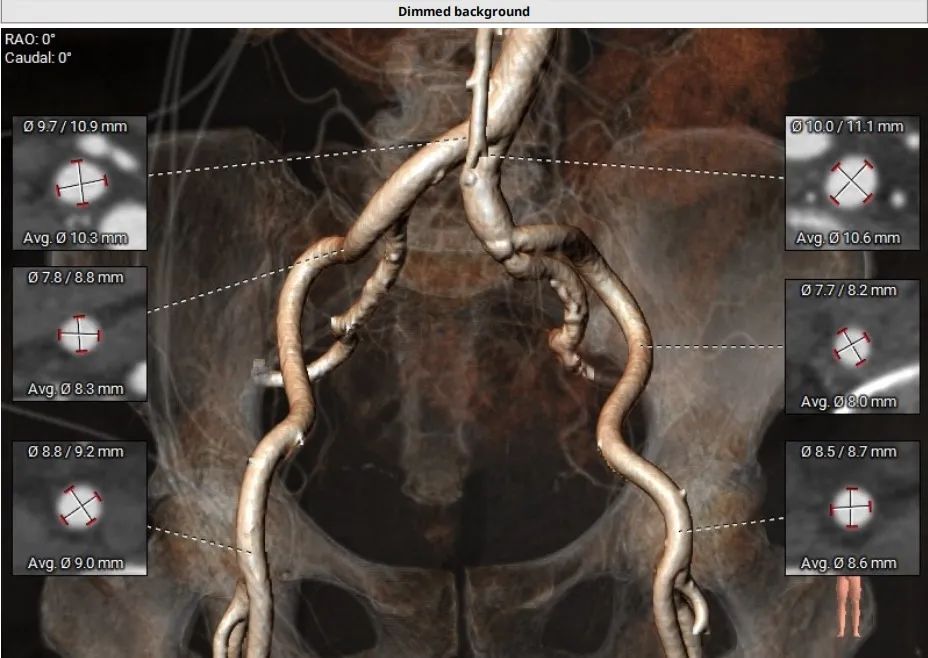

CT术前评估

主动脉根部情况

瓣环周⻓77.6mm,平均直径24.7mm    LVOT周长74mm,均径23.6mm

瓣上2mm--8mm 瓣上结构

左冠高度6.4mm 右冠脉高度12.3mm

♦ 三叶氏主动脉瓣,瓣叶增厚,重度钙化,主要分布于无冠窦及右无瓣叶交界处,瓣膜锚定力充足;

♦ 左右冠脉开口高度分别为6.4mm和12.3mm,左右瓣叶长,冠脉风险高,需球扩时评估是否需要冠脉保护;

♦ STJ直径34.8mm,高度18mm,稍偏低;升主动脉及弓角度OK,有一小块钙化,使用微创VItaFlow Liberty™瓣膜通过性顺畅

♦ 患者主动脉瓣环水平角度63°(横位心),器械过弓跨瓣会存在一定的困难,计划提前预埋Snare辅助

♦ 双侧髂总动脉走行尚可,股动脉入路两侧血管轻度迂曲,未见明显钙化,分叉高度可,左侧血管平均最小内径8.0mm,右侧血管平均最小内径8.3mm。预计采用右股为主入路,左股为辅入路

♦ 依据瓣环及瓣上分析结果,计划采用微创Alwide 20mm球囊预扩张,预植入TAV24瓣膜